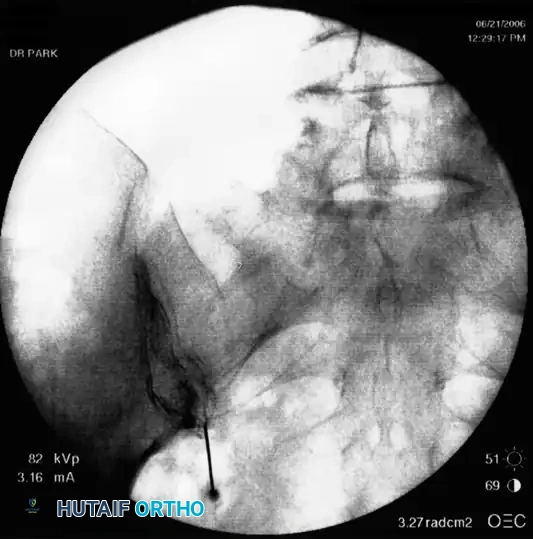

- Epidurogram Confirmation: Inject the contrast under live fluoroscopy to produce an epidurogram. Adjust the C-arm to a lateral perspective to definitively document posterior epidural spread and rule out intrathecal or intravascular flow.

- Contrast Flow: Remove the stylet. Aspirate vigorously. Inject 0.5 mL of nonionic contrast under live fluoroscopy. You must observe filling of the oval neuroforamen and distal flow along the exiting nerve root. If rapid vascular washout is seen, abort the procedure immediately.

The interlaminar approach in the thoracic spine requires a steeper paramedian trajectory to bypass the overlapping laminae. Fluoroscopic confirmation with a lateral epidurogram is mandatory to ensure the injectate remains posterior to the thecal sac, avoiding cord compression.

- Contrast Injection: Live fluoroscopy during contrast injection must demonstrate medial flow into the epidural space and lateral flow outlining the exiting spinal nerve.